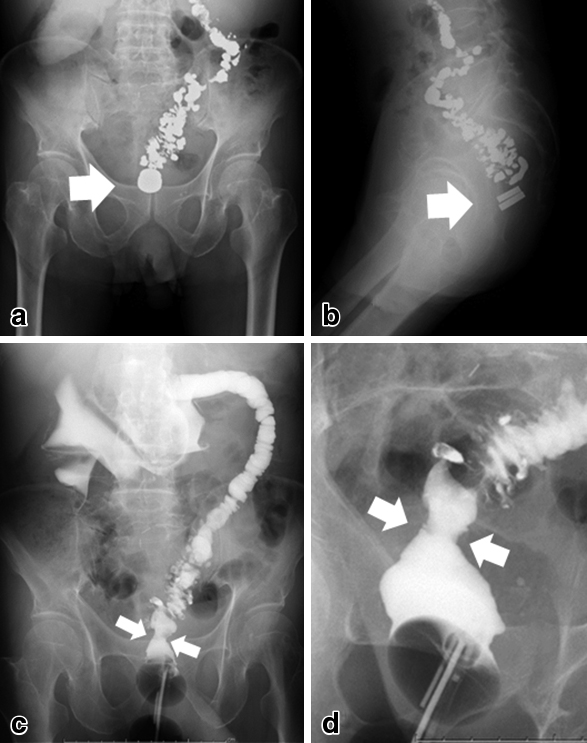

Study after the Yamanouchi method. a, b) On day 5, two magnets sandwiched the occlusion area (arrows). c, d) On day 8, both magnets were removed and eliminated. The diameter of recanalization was the same as the magnets (arrows).

施術後5日目では圧迫磁石にずれはなく(Fig. 4a, b),8日目に肛門から圧迫磁石の脱落があり,閉塞部組織は両磁石に圧迫壊死した形で排出され,使用した磁石と同直径の開通を得た(Fig. 4c, d).再狭窄を防ぐために,再開通部が安定するまでは,外来で2週間毎に3か月間,硬性ブジーによる拡張を行った.二つの磁石に圧着されて脱落した閉塞部組織は,直腸の線維組織として矛盾なく,悪性所見はなかった(Fig. 5).

Eight days after the Yamanouchi method. a) The two magnets squeezing the occlusion area dropped out from the anus. b) The tissue of the occlusion and magnets were the same size. c) Histologically, the mucosal epithelium is completely exfoliated. Scattered foreign bodies containing bacteria is found on the surface (arrow). Strong fibrosis is observed in the stroma without vascular structure (HE c: 4× d: 20×).